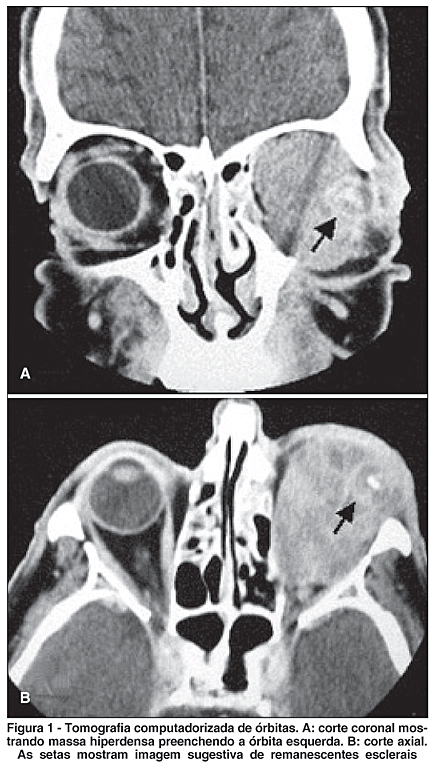

Paciente do sexo masculino, 64 anos, apresentou massa em cavidade anoftálmica esquerda há 5 meses, com crescimento progressivo e sangramento da lesão. O olho esquerdo foi eviscerado na infância devido à perda visual associada à inflamação de causa desconhecida. Ao exame apresentava massa endurecida e protrusa em órbita esquerda. A tomografia computadorizada de órbitas revelou massa lobulada, hiperdensa, com calcificações periféricas, erodindo parede medial, assoalho e teto da órbita esquerda, invadindo seios paranasais (Figura 1). Foi submetido à biópsia incisional que revelou tratar-se de melanoma maligno com padrão celular misto, constituído por células epitelióides e fusiformes. Não havia evidências sistêmicas de metástases. Realizou-se, então, exenteração orbitária esquerda. A avaliação histopatológica do material demonstrou que o tumor foi completamente ressecado e apresentava nítida adesão escleral. Após 4 meses nova investigação sistêmica mostrou nódulos pulmonares de origem metastática.